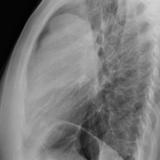

Case 1a

Thymoma

Date: 03/17/2004

Views: 4916